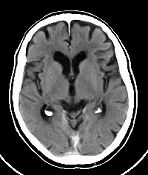

Und hier meine CT Aufnahmen...

Vielleicht sind hier ja ein paar Spezialisten die mir mehr sagen können.

Ich finde ich hab auch so wenig furchen, zB wie hier beschrieben...

Und was mir auch auffällt das ich an den Seiten diese furchen nicht habe....

Wär schön wenn mir jemand mehr sagen könnte.